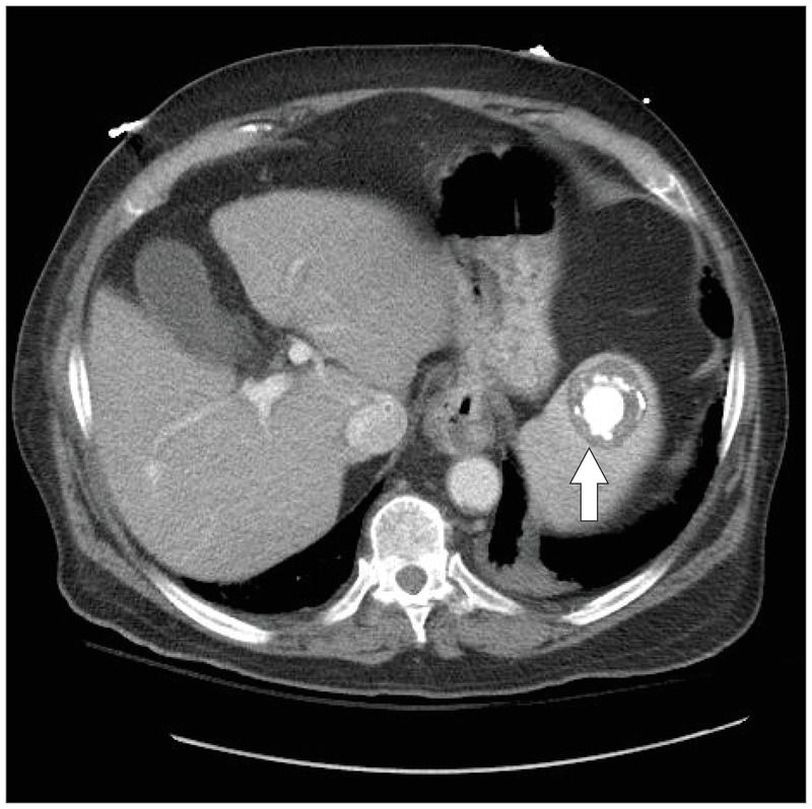

An 86-year-old man in Minnesota presented with fever, dyspnea, and new-onset confusion. His physical examination was unremarkable. His medical history was notable for a self-limiting febrile illness with night sweats and a weight loss of 23 kg (50 lb) that had occurred while he was in his late 20s and working in an abattoir slaughtering pigs. Computed tomography of the abdomen and pelvis revealed a coarsely calcified, circumscribed structure in the spleen that measured 4.5 cm by 4.2 cm by 2.8 cm (arrow). Blood cultures were positive for Brucella suis. Given the patient’s clinical history and positive laboratory findings, this lesion was consistent with splenic brucellosis. The patient was treated with a combination of doxycycline, rifampin, and trimethoprim–sulfamethoxazole and had a good recovery over a period of 10 days. We suspect that this was a case of reactivation of previous brucellosis. Lifelong antimicrobial suppression with doxycycline is planned in order to prevent recurrence.